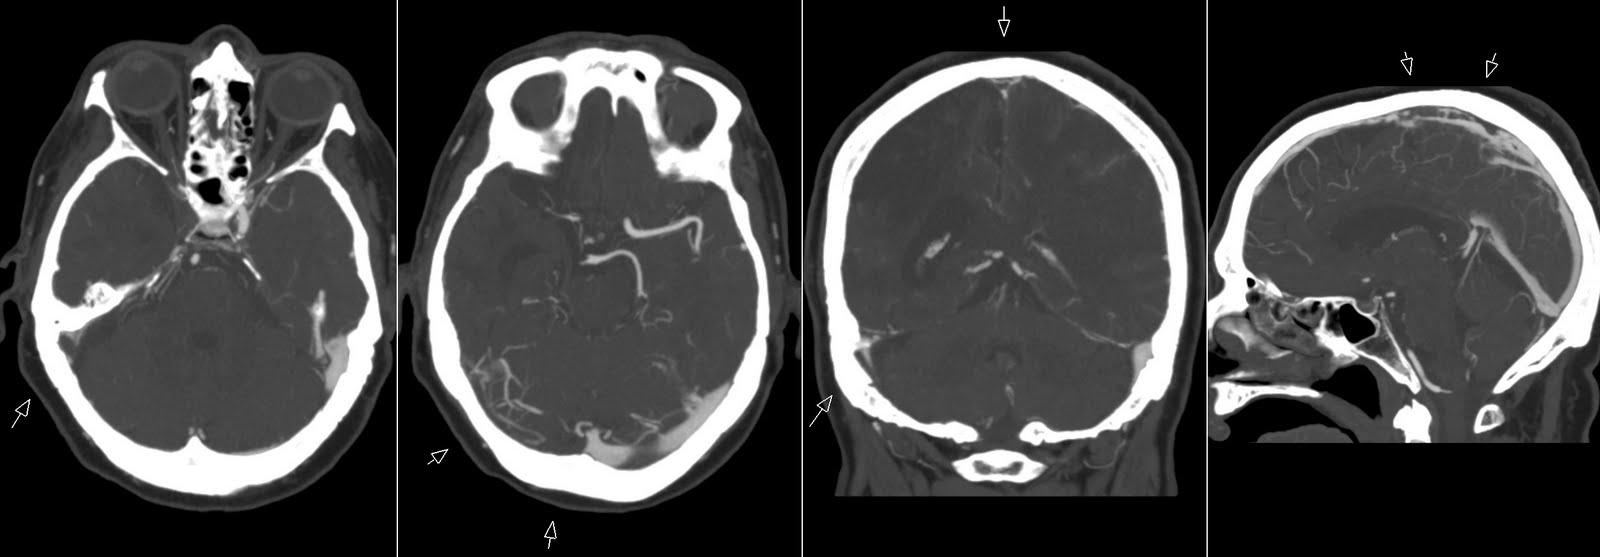

Дегенерация синуса

Дегенерация синуса 83 фото